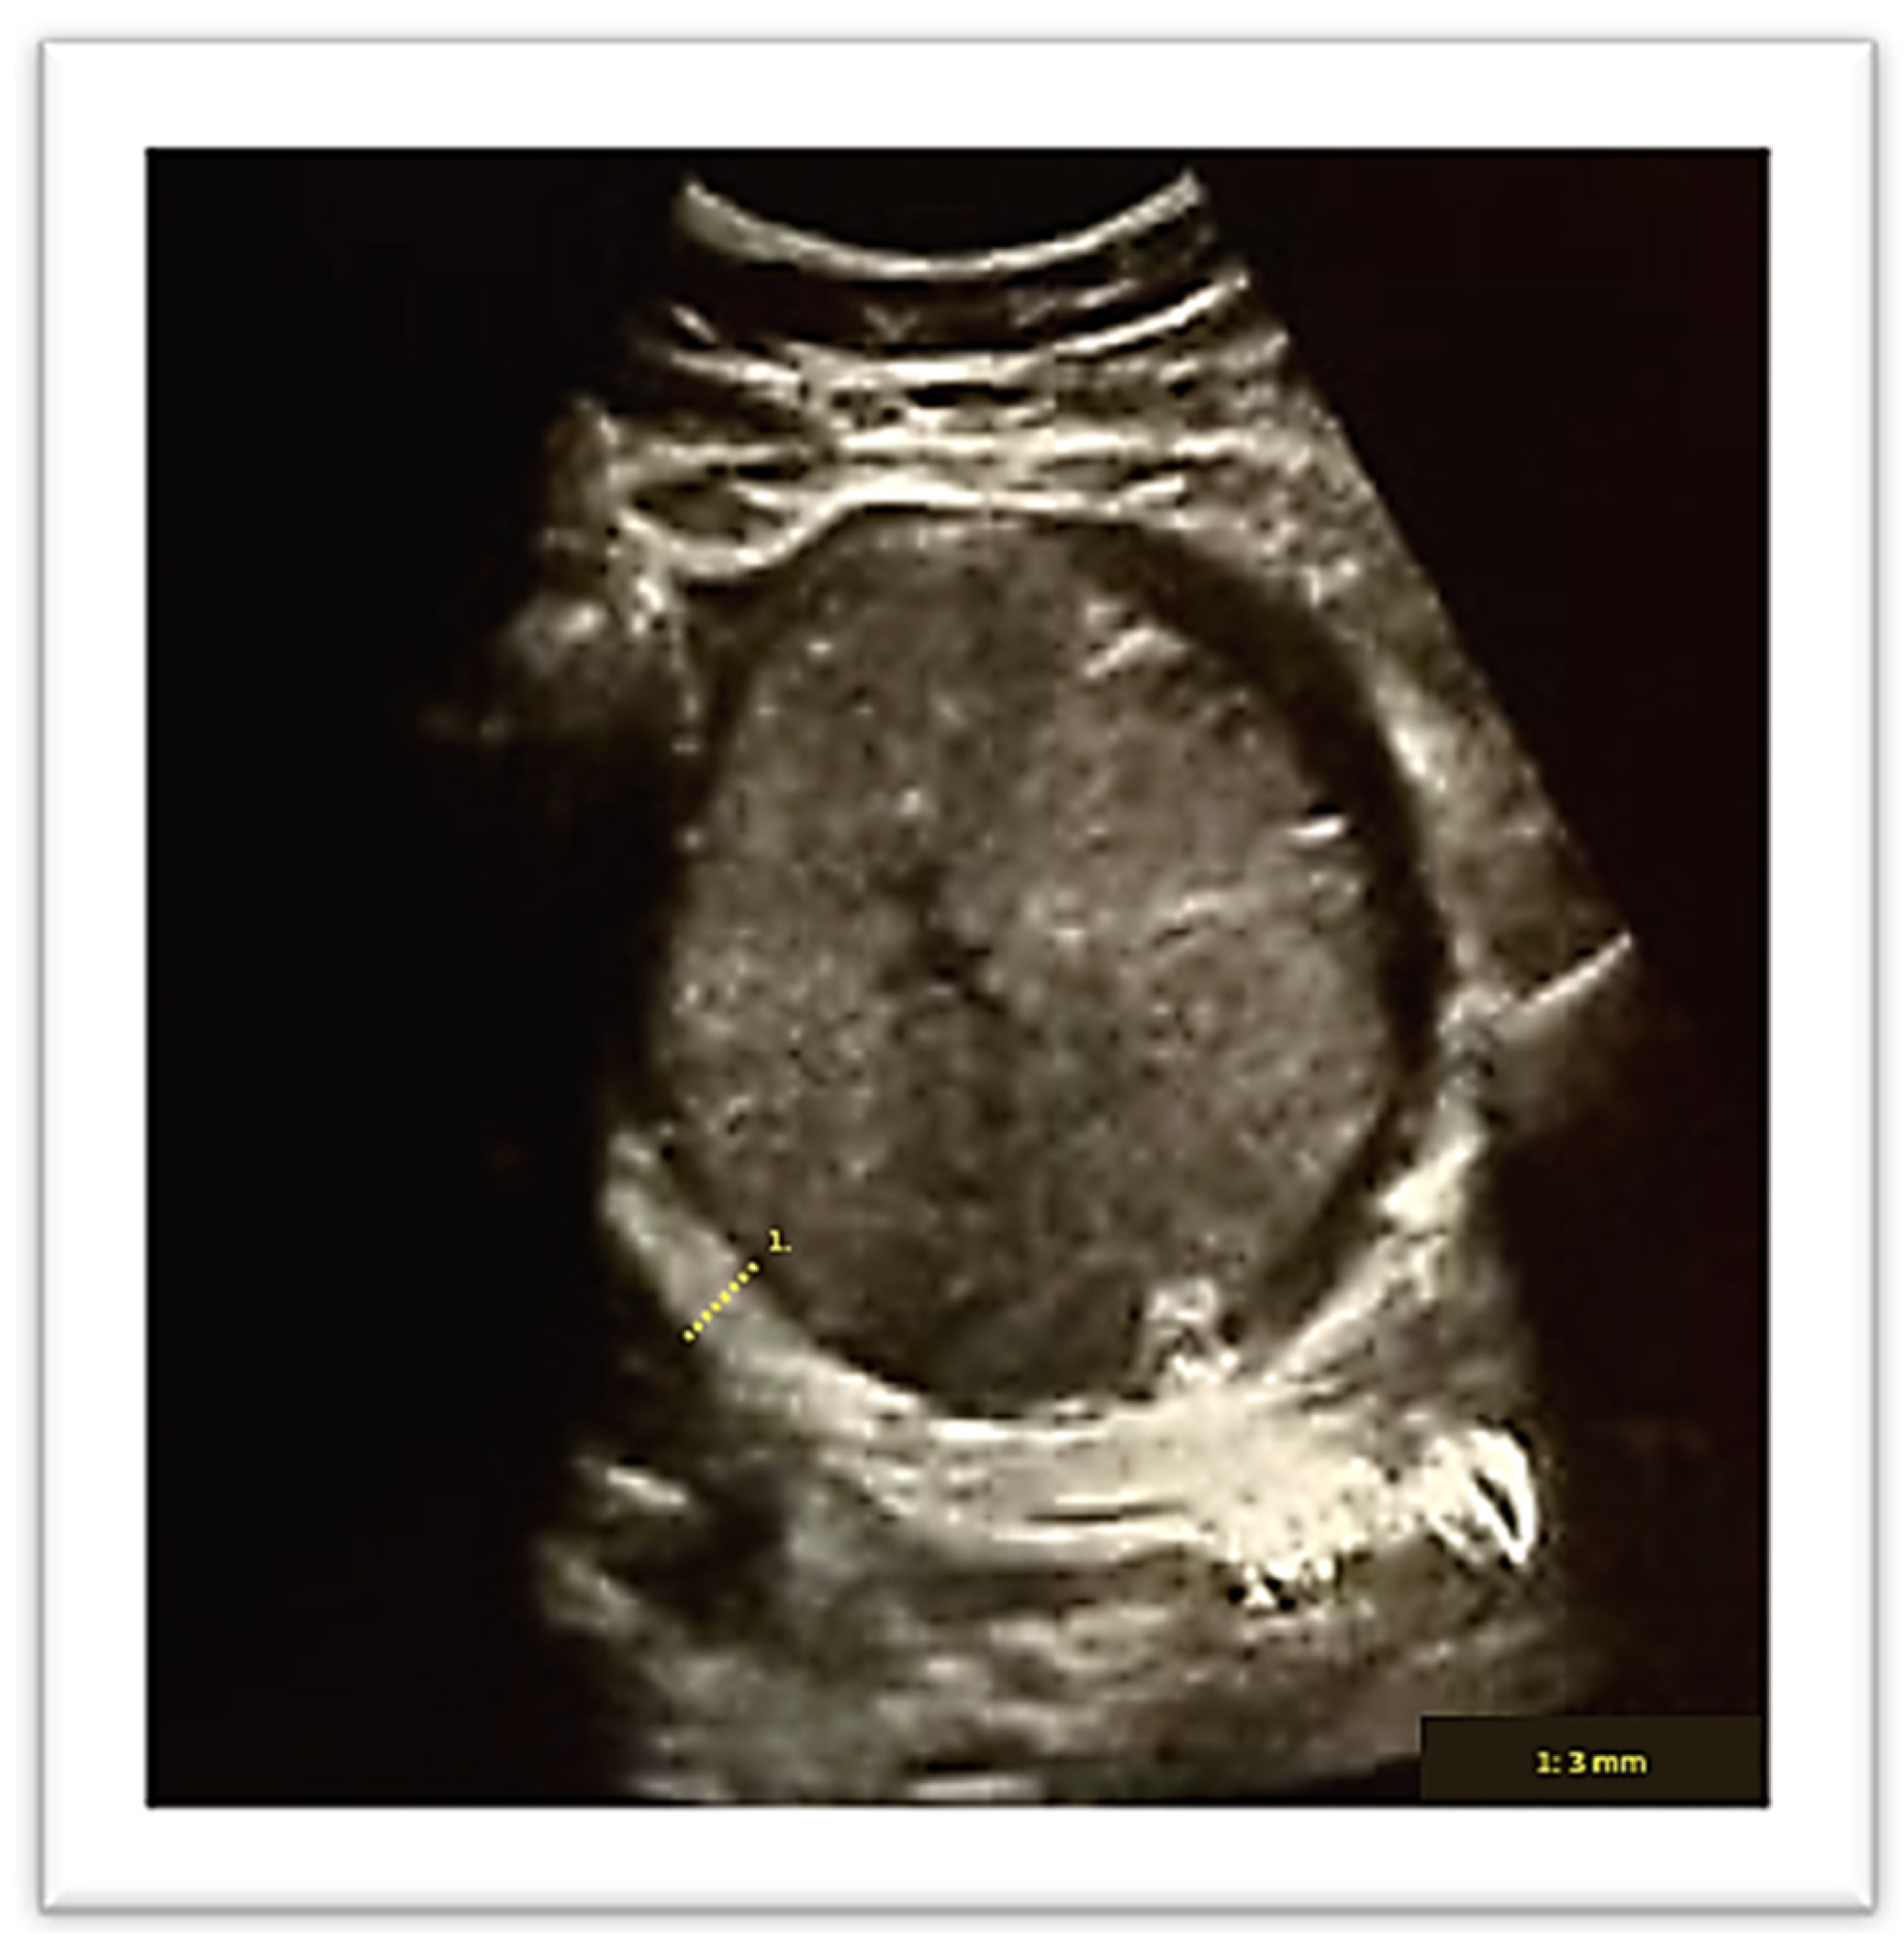

Pregnancy was complicated by a late-onset intrauterine growth restriction according to the most recent diagnostic criteria of the International Society of Ultrasound in Obstetrics and Gynecology (ISUOG) [11] (estimated fetal weight below the 3rd centile with abnormal uterine arteries Doppler). At hospital admission upon ultrasound review, the placenta appeared to be located in the upper right lateral side of the uterus (Figure 1).

Figure 1. Ultrasound evaluation of placenta location.